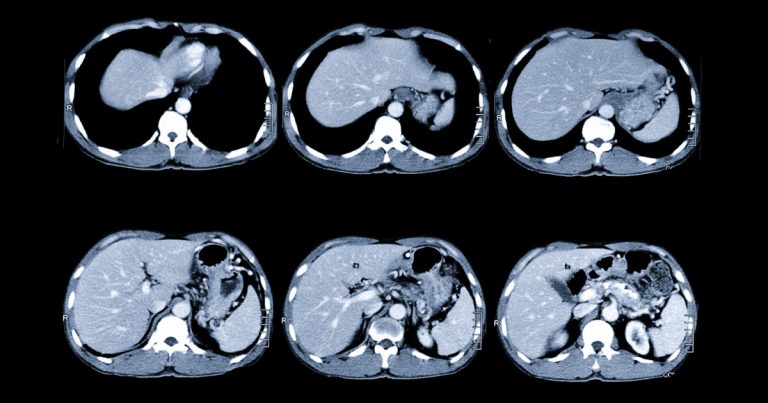

Підготовка до КТ черевної порожнини: дієта та «голодний» режим

Статті Автор: Ан-Сі-Тек Тетяна

Комп’ютерна томографія (КТ) черевної порожнини — це швидкий і точний спосіб оцінити стан внутрішніх органів. Але якість результату залежить не лише від апарата та лікаря, а…

Читати →

КТ черевної порожнини: ознаки гострого апендициту та панкреатиту

Гострий біль у животі — одна з найчастіших причин звернення по медичну допомогу. У таких ситуаціях важливо швидко встановити причину, адже деякі стани потребують невідкладного лікування.…